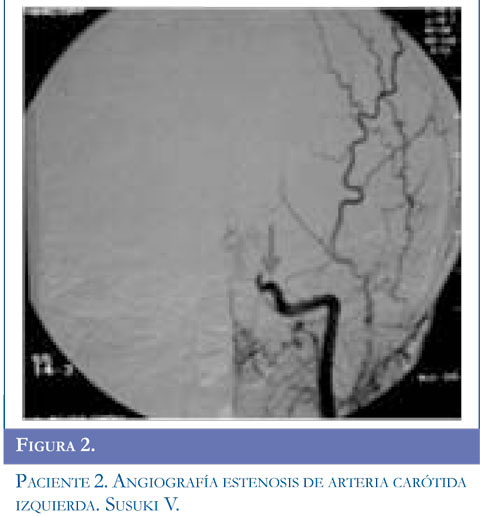

Ingresa al servicio de urgencias por presentar alteración de la marcha dado por disminución de la fuerza en hemicuerpo derecho y dificultad para el habla, acompañado de movimientos clónicos de miembro superior derecho, sin perdida de conciencia la mirada de 10 segundos de duración, se repiten en 5 oportunidades y ceden con benzodiacepinas. Se inició manejo anticonvulsivante. Al examen tenía parálisis facial derecha periférica, hemiparesia derecha con hiperreflexia músculotendinosa, disimetría, disdiadococinesia ipsilateral y afasia motora. Se realizó TAC simple de cráneo y contrastado con lesión gangliobasal izquierda de características isquémicas. Presentó clonias de brazo y aumento de la debilidad faciobraquial derecha, hemianopsia heterónima derecha, se realizó RMC con hipodensidad parieto temporal izquierda compatible con lesión isquémica en territorios de arteria cerebral media izquierda. Se inició enoxaparina1mg/k/dosis y calcio antagonista. El perfil hematológico fue normal. La panangiogra-fía evidenció enfermedad de Moyamoya estadio V de Suzuki. Valorado por neurocirugía se consideró manejo quirúrgico y el día 19 del cuadro clínico se realizó encefaloduroarteriosinangiosis. En la actualidad tiene afasia motora en mejoría, hemiparesia derecha y componente distónico ipsilateral, hiperre-flexia derecha, continúa manejo con fisiatría, terapia física, ocupacional y del lenguaje. Figuras 1,2 y 3.

Para el estudio de esta enfermedad ante la sospecha clínica se deben solicitar estudios radiológicos como tomografía computarizada de cráneo (TAC) evidenciando áreas pequeñas de hipodensidad que sugieren hemorragia o isquemia en región cortical, ganglio basal, profundidad de sustancia blanca o región periventricular; sin embargo, la TAC puede ser normal si el paciente presenta un evento isquémico transitorio. En todos los pacientes de esta serie, se solicitó TAC encontrandose lesión focal secundaria al evento vascular en regiones subcorticales y gangliobasales. La disponibilidad de RM y angiografía por RM se ha convertido en el método diagnóstico del síndrome de Moyamoya. Un infarto cerebral agudo es más probable que se detecte con el uso de imagen por difusión, un infarto cerebral crónico se observa en RM en T1-T2. El flujo sanguíneo cortical disminuido se observa en la secuencia FLAIR como una señal lineal intensa que sigue la forma de los surcos llamado "signo de la hiedra" (14). Los hallazgos más frecuentes en RM son reducción del flujo de la arteria carótida interna, arteria cerebral anterior y media hasta llegar a ausencia de flujo sanguíneo en ganglios basales y tálamo con formación de vasos colaterales; en este informe el examen confirmatorio se realizó con angiografía, se debe realizar estudio de 5 o 6 vasos que incluyan arterias carótidas externas, carótidas internas y 1 ó 2 arterias vertebrales según colaterales que se presenten. El diagnóstico definitivo se basa en el aspecto arteriográfico caracterizado por estenosis de la arteria carótida interna a nivel distal, extendiéndose a la región proximal y media (15). La severidad de la enfermedad se clasifica de I a VI estadios de progresión según el sistema de clasificación de Suzuky (16) (Tabla 1). En los casos presentados el grado de estatificación fue IV y V mientras que en la serie de González (5) existieron varias presentaciones I, III y VI; Galicchio (6) presentó casos en estadio II a III.